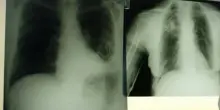

Strategie di immunizzazione contro il virus respiratorio sinciziale

L'urgenza di proteggere i neonati dal virus respiratorio sinciziale è più critica che mai. Leggi tutto Strategie di immunizzazione contro il virus respiratorio sinciziale su Notizie.it.